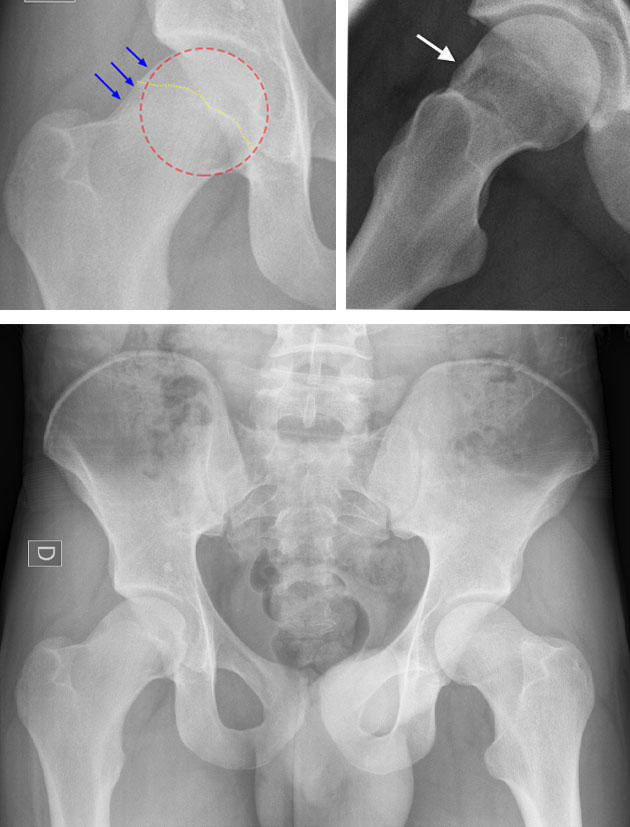

This results in increased actual and potential effacement of the femoral neck onto  the acetabular rim. Resultant local joint irritation (synovial and capsular) occurs,  with reflexic muscle adaptation and shutdown, as well as longterm kinematic  changes in pelvic and hip control. Hence the classic symptoms of pain in a 'C' sign distribution. Its diagnosis is usually from radiographic evidence (to assess whether  there is the presence of hip dysplasia or similar causes in change of hip morphology (CAM hip) or pincer impingement with labral damage) in combination  with clinical examination. However in the authors opinion, FAI should always be  considered a 'clinical' diagnosis (that is to say that it can exist without radiographic evidence). Copyright N.Potter

It has yet to be correlated but it is likely that there is also a direct relevance of the angle of Pelvic Incidence (PI) to the existence of FAI

Diagram showing angular measurements necessary for calculation of pelvic incidence (PI) Copyright; NPotter

Diagram to show relative angular positions of the pelvic landmark anatomy and the effects of variance therein.

When pelvic incidence is low then the hip joint sits more vertically underneath the lumbar spine reducing the clearance possible between the femoral neck and the anterior-superior acetabular rim. The resultant effect is the need for pelvic posterior rotation (retro version) to accommodate the impingement. This is in turn effectively flattens the lumbar lordosis.